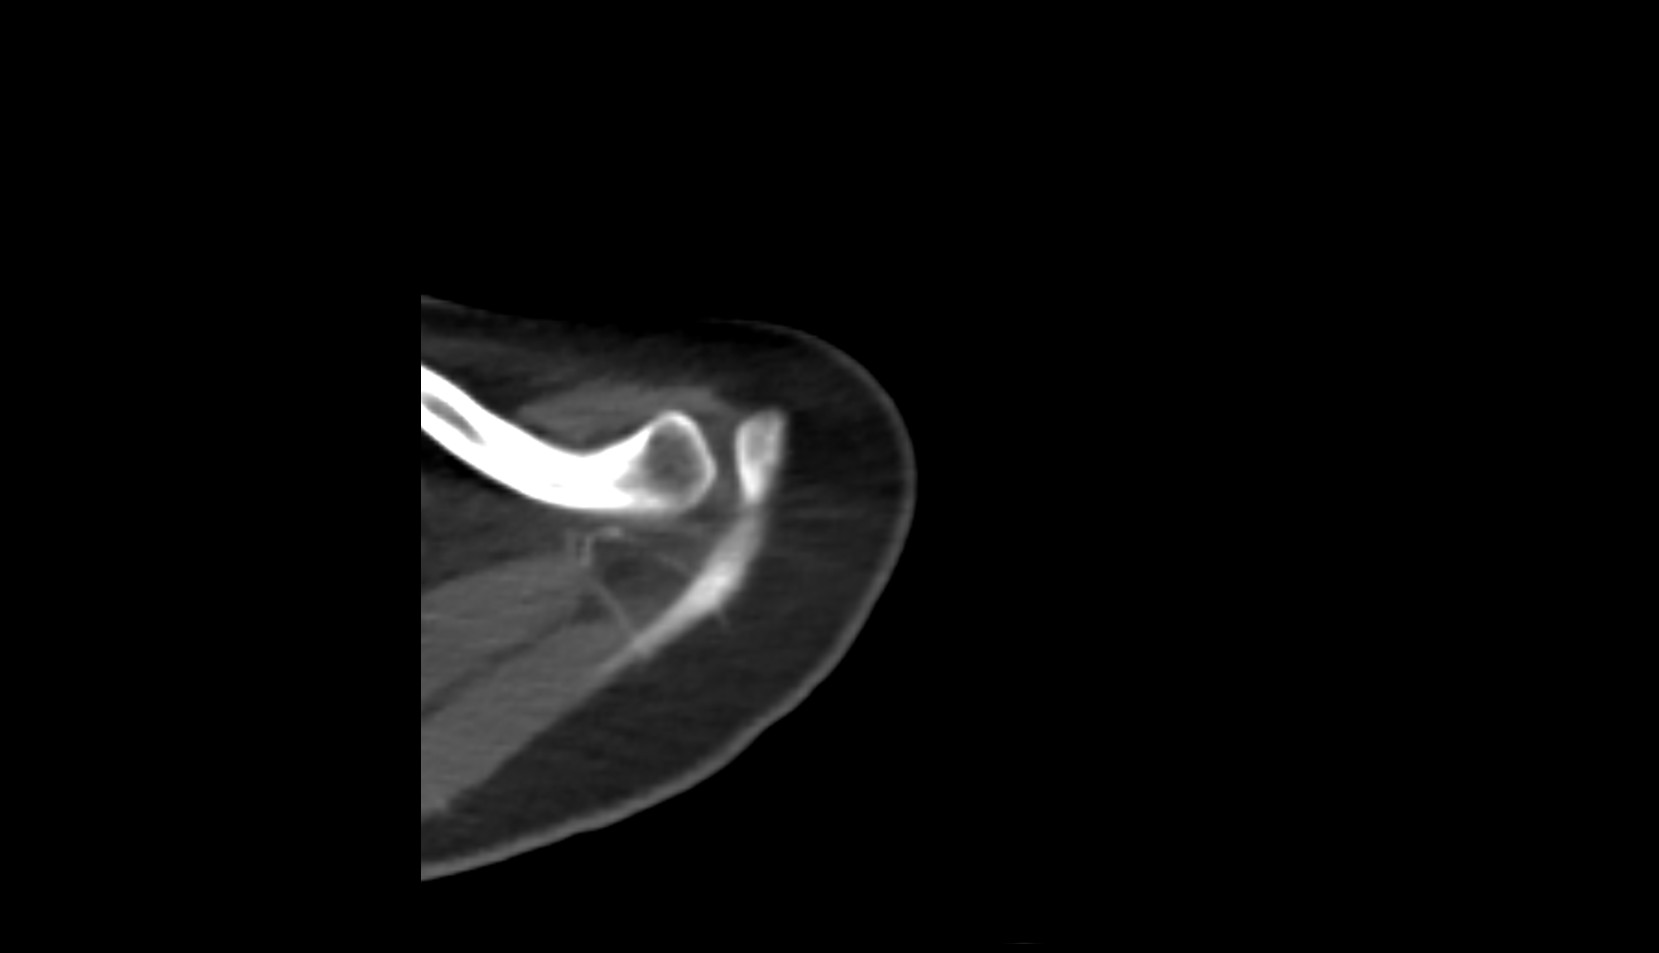

- Shoulder joint (glenohumeral joint)

- Acromioclavicular joint